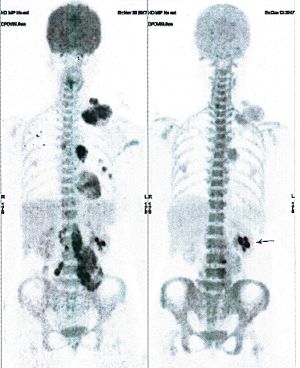

CASE NO: 3 (PROSTATE CANCER)

A middle-aged man with castration resistant prostate cancer, having failed all currently available cancer treatment, was very weak, and getting worse every day. The PET/CT scan showed he had massive bone metastases. After a few treatment, all the bone metastases went into remission. About 6 months later, he is still in remission.

CASE NO: 4 (PROSTATE CANCER)

A middle-aged man with castration resistant prostate cancer and massive bone metastases, failed all currently available cancer treatment, including with the new and expensive drug XTANDI. After a few treatment, most of the bone metastases went into remission, and the remaining ones are less active. Treatment will continue. Cases no: 3 and 4 show that terminal prostate cancer today can be cured with our new cancer treatment.